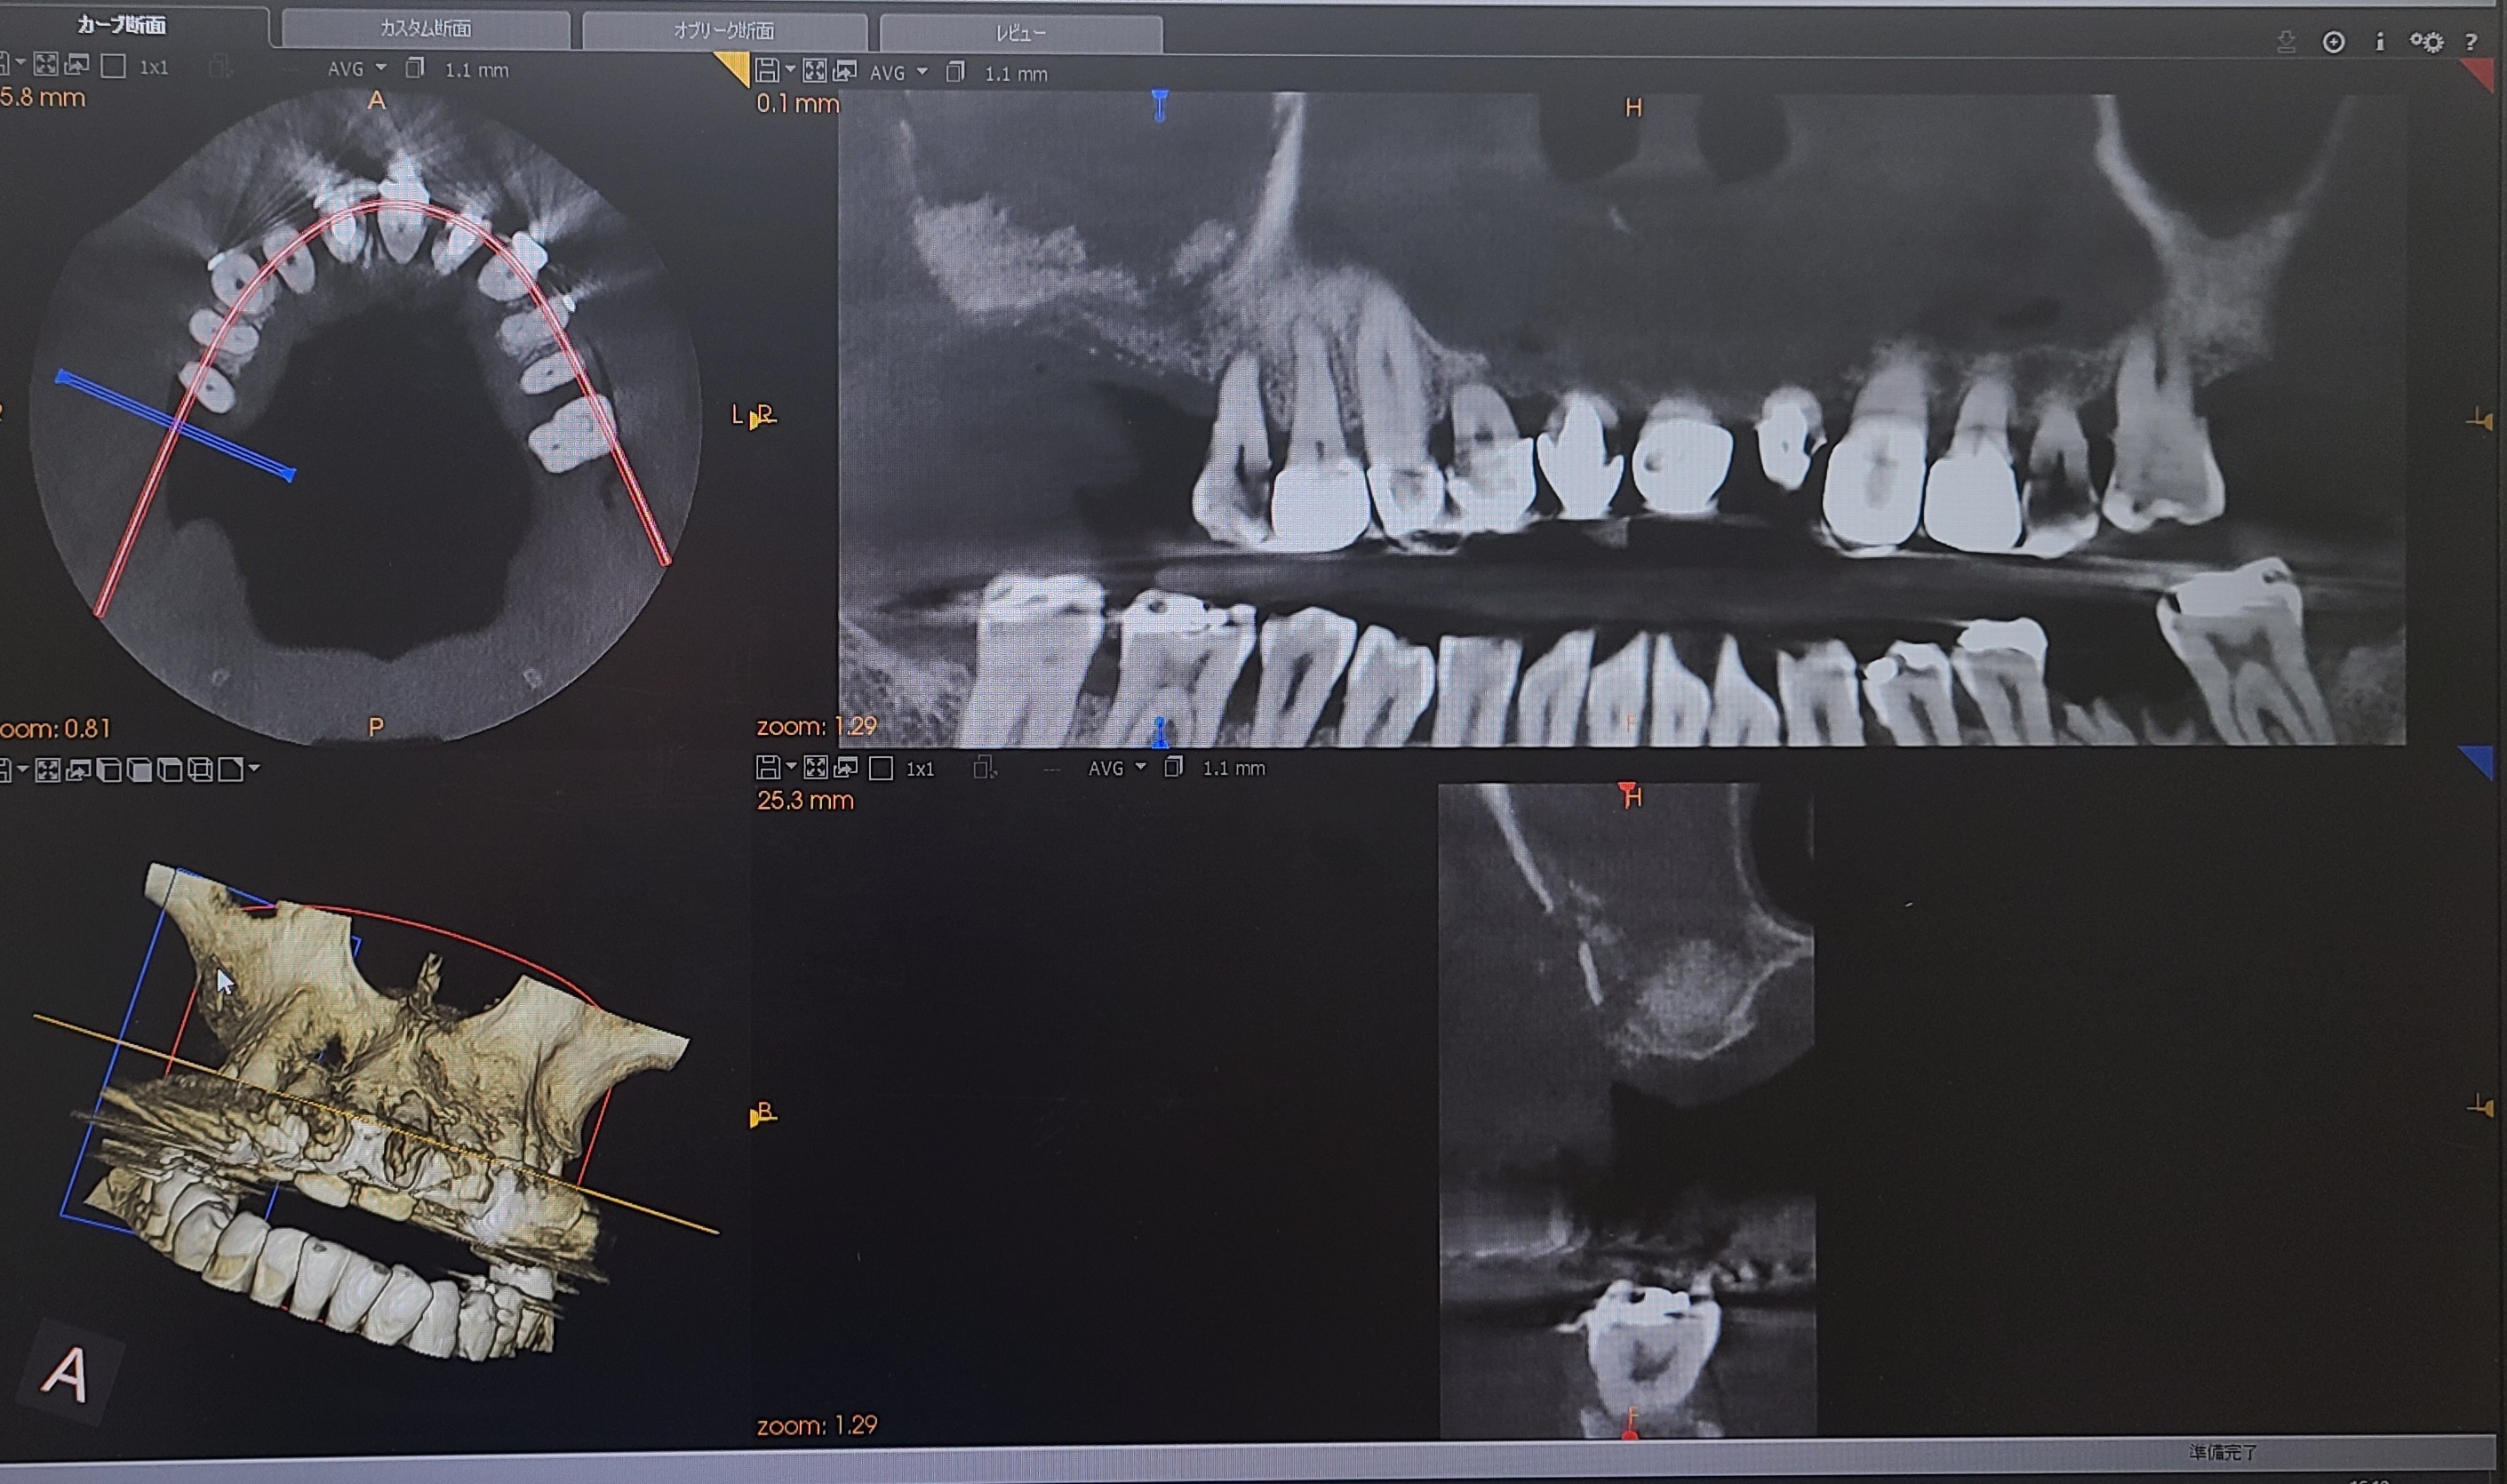

インプラント治療をするうえでまずはCTを撮影して骨があるかの確認をします

個人歯科医院ではまだまだ導入が少ないCT(コンピュータ断層撮影)でお口の中を撮影し、神経や上顎洞の位置を正確に把握し骨の状態を確認しインプラント治療計画をご提案します。 わかりやすい説明で、納得した上で安心して治療を受けていただけます。

1. CT撮影

CTとはX線を利用して体内の断面図を撮影する技術で、立体的に神経、血管、骨などの様子を把握することができます。

インプラント治療は骨がないと治療ができないため必ずCTを撮影して診断いたします。

骨の形や骨質、高さや幅には個人差があります。歯がどのように失ってしまったのかで変わってきます。

また、骨の中には神経や太い血管が通っていますので慎重に確認をしていきます。